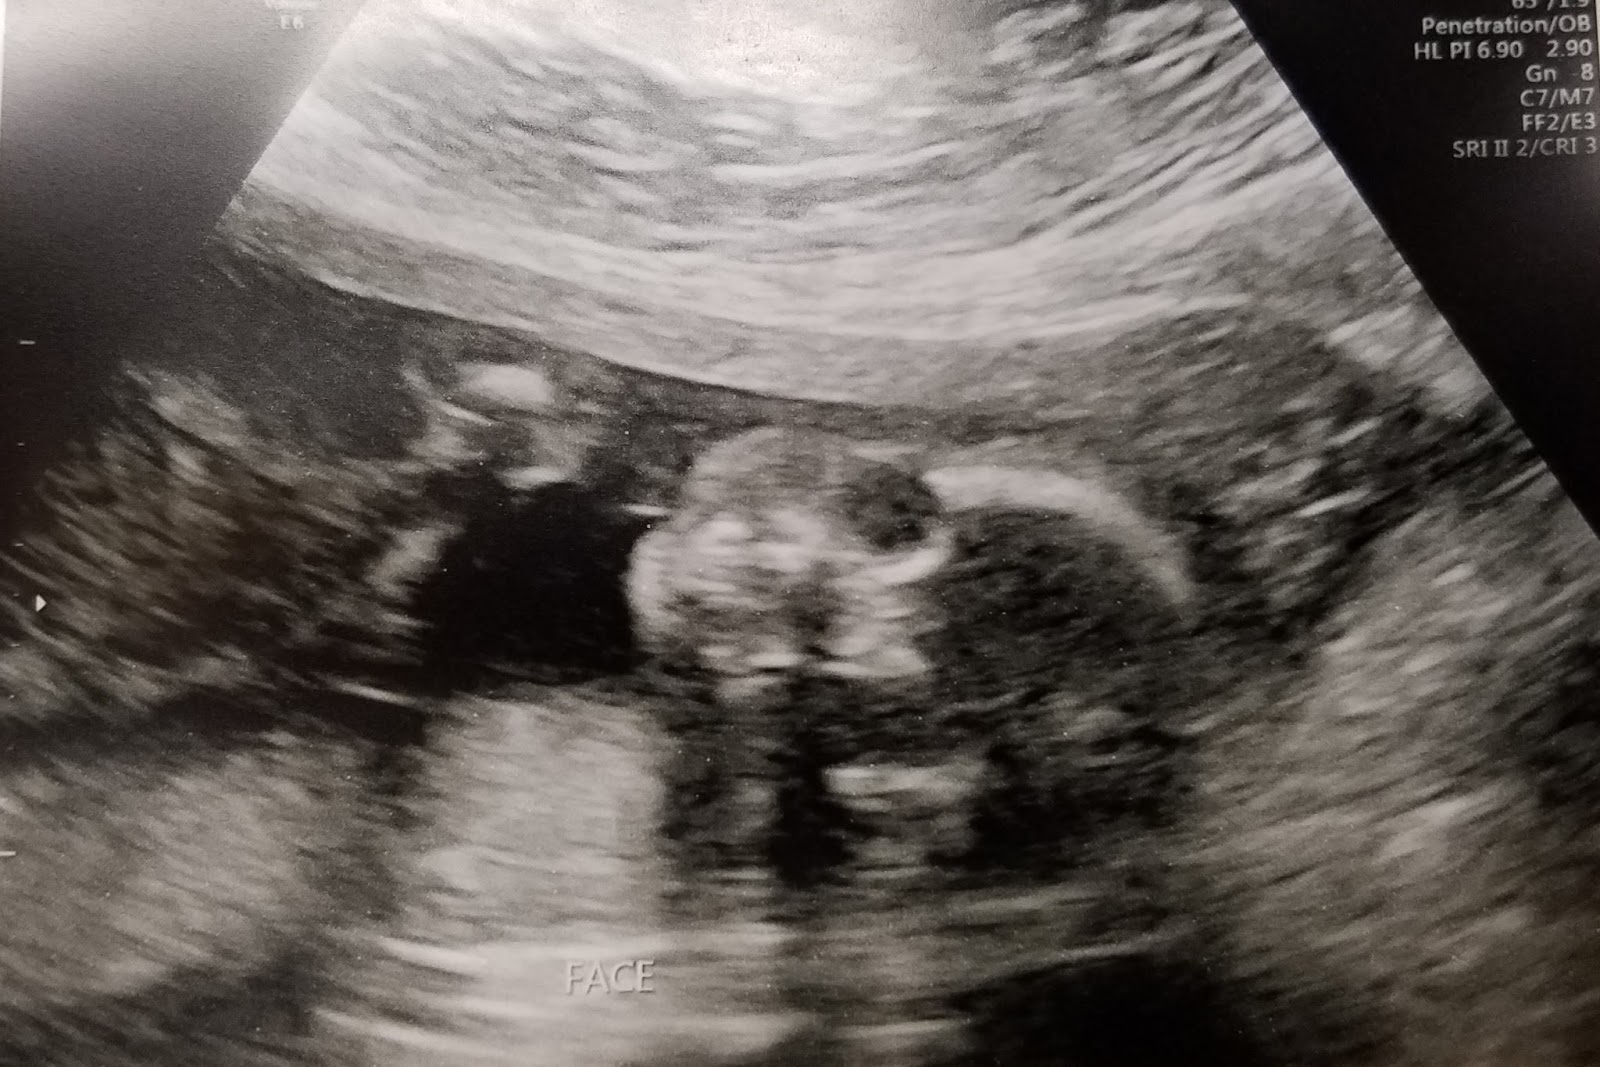

From community.whattoexpect.com

Skeleton face ultrasound October 2018 Babies Forums What to Expect Skeleton Face Ultrasound 2, frontal or metopic suture; Five basic views are used to assess the fetal head and neck: 3d ultrasound is an important tool for the evaluation of the fetal face in the first trimester. In fetus a, the ultrasound beam is perpendicular to the long axis of the face and clearly displays the nose with nasal bone, the maxilla, and. Skeleton Face Ultrasound.

Skeleton face ultrasound October 2018 Babies Forums What to Expect Skeleton Face Ultrasound In fetus a, the ultrasound beam is perpendicular to the long axis of the face and clearly displays the nose with nasal bone, the maxilla, and chin with mandible. 2, frontal or metopic suture; 3d ultrasound is an important tool for the evaluation of the fetal face in the first trimester. The different sutures and fontanelles are depicted in the. Skeleton Face Ultrasound.